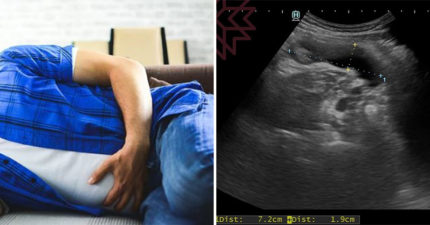

有腫瘤電腦斷層卻正常 醫檢查驚見「7cm大香腸」

October 13, 2022

台灣